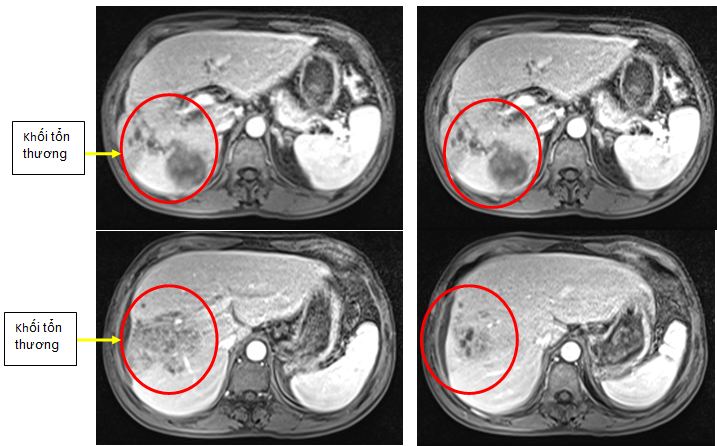

Bệnh nhân được chụp cộng hưởng từ gan mật: gan to, tổn thương lan tỏa gan phải kích  thước khoảng 10cm, giảm tín hiệu trên ảnh T1W, tăng không đồng đều trên ảnh T2W dạng các hốc dịch nhỏ. Sau tiêm thuốc đối quang từ, tổn thương này ngấm thuốc ở vách. Ngoài ra có hình ảnh máu tụ dưới bao gan phải dày khoảng 5cm, có ít dịch tự do ổ bụng

Hình ảnh chụp cộng hưởng từ: Hình ảnh tổn thương lan tỏa gan phải kết hợp với máu tụ lớn dưới bao gan phải, nghĩ nhiều tới tổn thương do ký sinh trùng